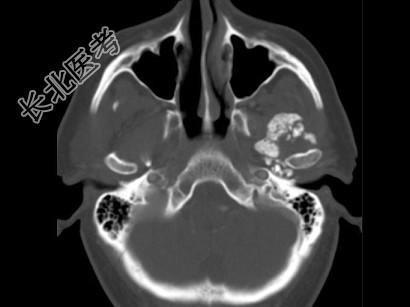

- 多项选择题男,60岁, 张口受限半年,CT检查如图所示, 正确的描述或诊断是 ( )

A、左侧颞颌关节周围软组织内见较多致密钙化影

B、左侧颞颌关节软组织未见肿胀

C、左侧颞颌关节面(颞骨面)骨质增生明显

D、左侧颞颌关节滑膜骨软骨瘤病

E、颞颌关节功能紊乱